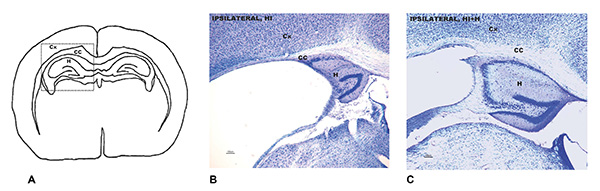

A: zona del cerebro afectada por la lesión cerebral por hipoxia e isquemia. B: Análisis neuropatológico que muestra el daño cerebral en ratones adultos que siendo bebés sufrieron la lesión y no recibieron estimulación sensorial. C: Análisis neuropatológica de la misma zona en los ratones adultos que sí la recibieron.

Los resultados muestran que esta intervención ejerce una notable protección neurológica en ambos sexos a lo largo de la vida, pero es especialmente positiva en el sexo masculino, destacan las investigadoras. En este sexo, el análisis histopatológico mostró un daño cerebral un 50% menor que en los ratones no sometidos a la estimulación. En las hembras fue de un tercio. La protección neurológica en ambos sexos se correlacionó con mejoras en las capacidades funcionales, a nivel de reflejos, y permitió mejorar los resultados de memoria.

Por áreas cerebrales, la región involucrada en el control motor y el aprendizaje y la memoria -el caudado-putamen-, fue la que registró una mayor diferencia en machos, con un 80% menos de afectación. En hembras, la principal mejora fue la disminución, en un 66%, de la atrofia del cuerpo calloso, que permite a los dos hemisferios cerebrales trabajar de forma conjunta y complementaria.